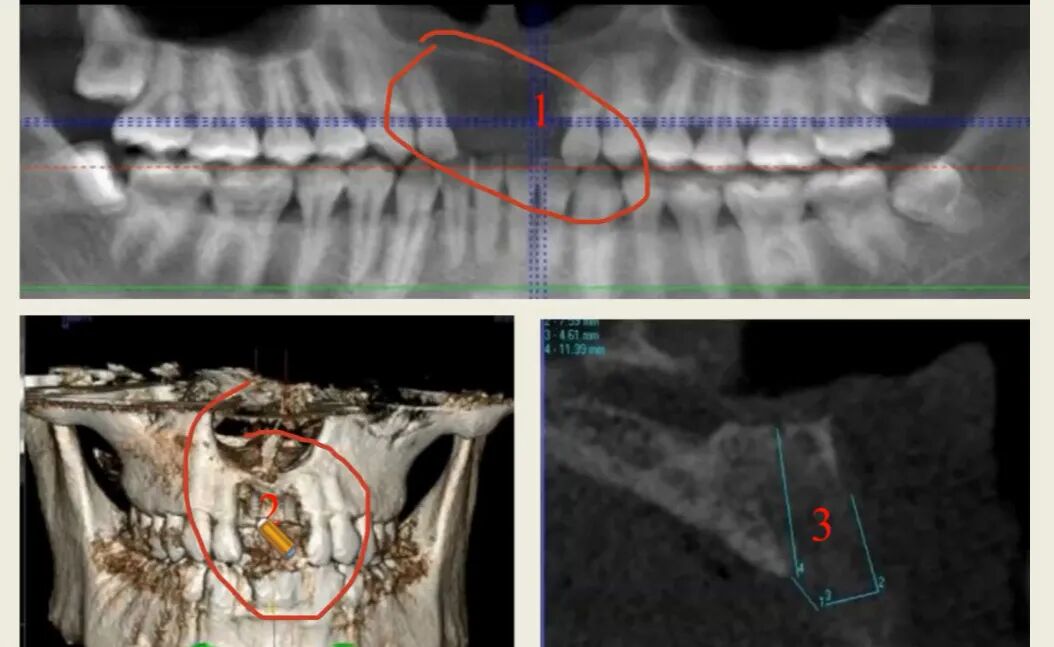

CBCT具体测量方法和容易陷进去的误区

CBCT用十字交叉法测量骨数据,可精准应用于双皮质固位。但有时CBCT也会让人判断不清骨缺损或骨密度低,例如下图:拍了CBCT并进行了重建,发现骨缺损,但牙槽嵴顶丰满度良好,这是因为拔完牙后骨密度还没有形成,但旁边牙齿骨密度高,对比太明显,CT把密度低的部分剪掉了,结果显示缺损,可以拍侧貌图3,可以看到轮廓,完全可以种植,所以一定要准确判断骨缺损还是骨密度低。